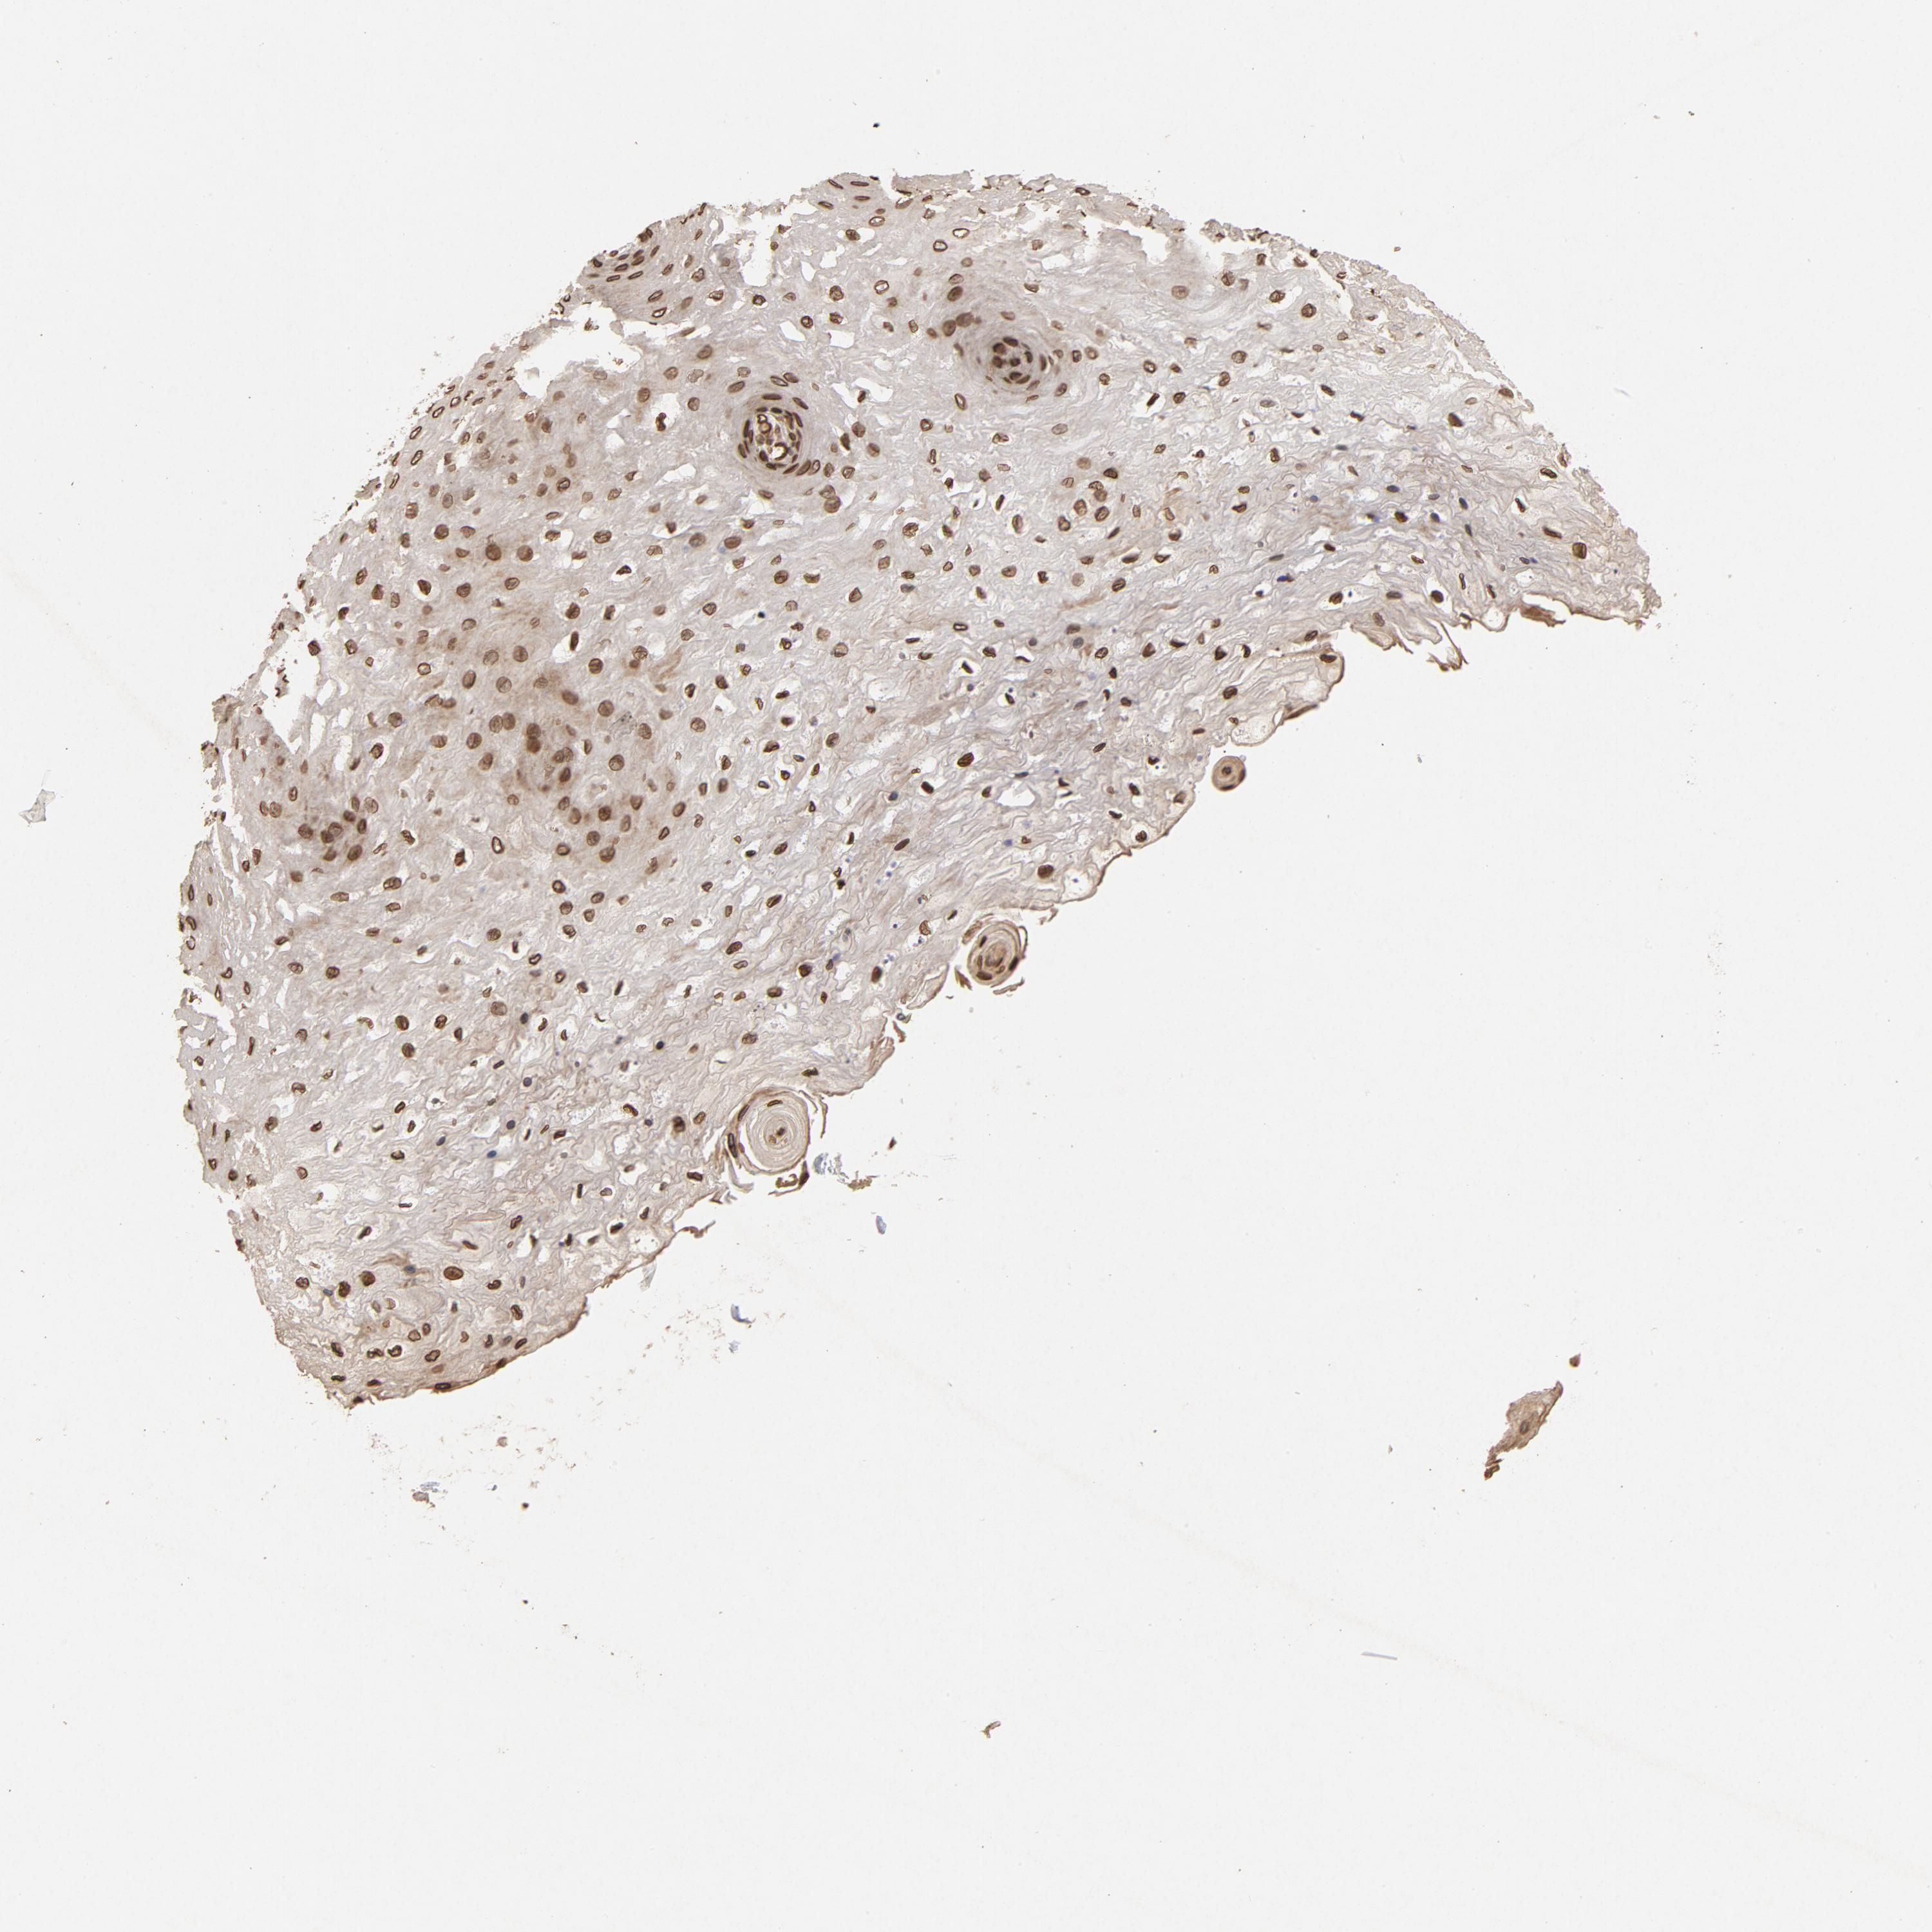

ESOPHAGUS - Antibody stainingi

Antibody staining in the annotated cell types in the current human tissue is reported as not detected, low, medium, or high, based on conventional immunohistochemistry profiling in selected tissues. This score is based on the combination of the staining intensity and fraction of stained cells.

Each image is clickable and will lead to virtual microscopy that enables deeper exploration of all samples and also displays staining intensity scores, fraction scores and subcellular localization as well as patient and tissue information for each sample.

Antibody HPA006660Antibody CAB004022

Squamous epithelial cells HighHigh